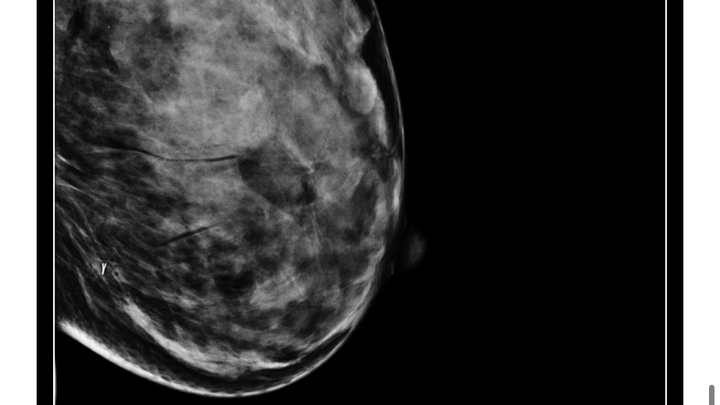

My name is Queen, I am am a disabled cannabis educator from DC whose lived in MD the majority of my life, I am 1/2 of Dispense Throne, lab technician and mother of an Autistic 13 year old and wife; in other parts of my life, I’m known as DQ and have dedicated the last 15 years of my life towards cannabis education, advocacy while in pursuit of a cannabis license in MD, this has involved doing lots of mutual aid and donations towards other folks who needed assistance from legal, personal and financial and recently I’ve been diagnosed with Stage 2b Infiltrating Ductal Carcinoma in Situ with a nuclear grade 2/3 tumor in my left breast.

Self Breast Exams find 40% of Breast Cancers that start with a lump

Breast Cancer timeline:

Original complaint of pain in breast: 2/10/23

Self-Breast Check: 11/10/24

Ultrasound and Mammogram: 12/17/24

Multi Site Biopsy: 12/16/24

Pathology & Surgical Referral: 1/9/25

Surgical Consultation for Lumpectomy: 12/21/25